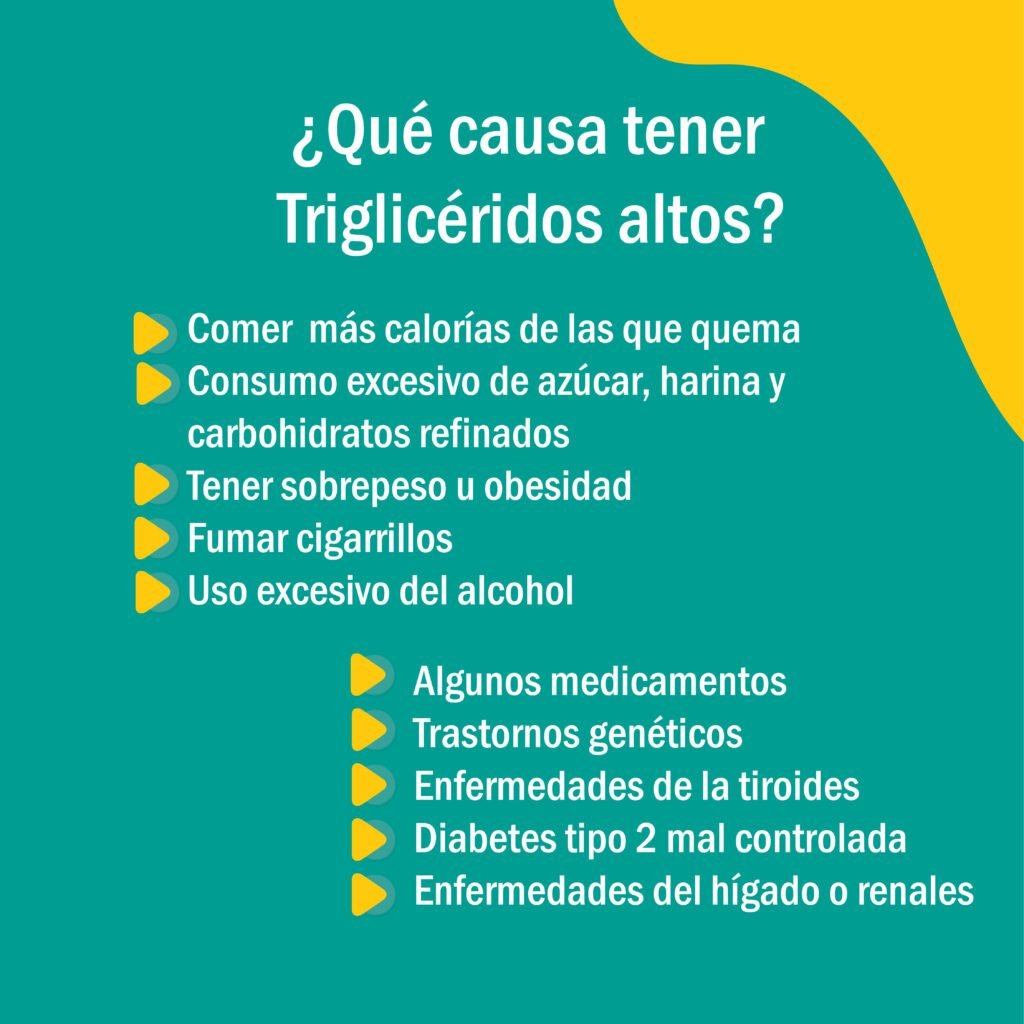

Cuando se miden los triglicéridos se toman en cuenta los que provienen del intestino y del hígado, y que también pueden generarse por causas genéticas (primarias) o causas según diferentes factores (segundarias).

Si los niveles de triglicéridos están entre 150 – 300 mg/dL, lo más probable es que sea por problemas segundarios como: diabetes, síndrome metabólico, algún daño renal, incluso, puede derivarse de una ingesta excesiva de azúcares refinados, grasas, consumo de alcohol o algún efecto de un medicamento.

Si los triglicéridos se encuentran entre 300 – 500 mg/dL se podría sospechar de una causa genética. Es decir, una causa primaria. Esto dependerá de un diagnóstico específico ya que no todas las elevaciones de triglicéridos obedecen a la misma causa genética. Dependiendo de cual sea la causa puede ser su severidad. Por ello, se requiere un diagnóstico completo.

Si sus niveles de triglicéridos son entre 1000 – 5000 mg/dL se puede hablar de una causa de Quilomicronemia, la cual es un trastorno en donde el cuerpo no descompone las grasas (lípidos) correctamente. Esto hace que las partículas grasas llamadas quilomicrones se acumulen en la sangre.